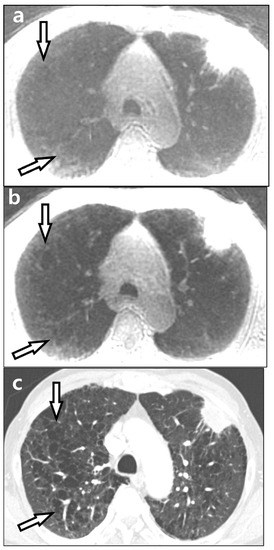

3.3. Lesion Detection